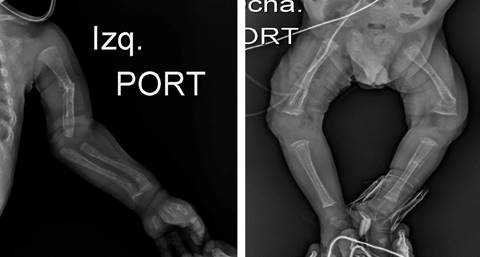

A los 62 días de vida presenta episodio de deterioro respiratorio, por lo que se realiza radiografía toracoabdominal en la que se evidencia disminución de la densidad radiológica ósea con presencia de signos de desmineralización, en particular deshilachamiento de metáfisis de húmero (Figura 1). Al tomar otras radiografías de las extremidades se evidenciaron múltiples fracturas de huesos largos, con signos de pérdida de línea metafisaria, desmineralización, deshilachamiento, imágenes en cáliz de copa (Figura 1).

Figura 1: Evaluación inicial: radiografías de huesos largos. Fractura diafisaria del húmero izquierdo, levemente angulada con esclerosis en el sitio de fractura, angulación metafisaria distal de cúbito y radio izquierdo sugiere fractura no desplazada. Fractura metafisaria distal del fémur izquierdo, levemente angulada. Fractura epifisaria de la tibia y el peroné izquierdo, no desplazada, con esclerosis en el sitio de fractura.